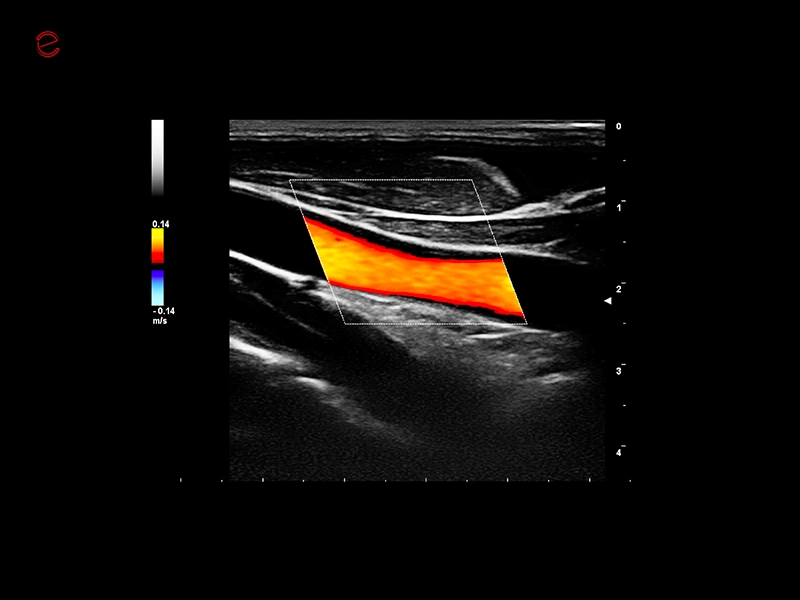

High-quality imaging on-the-go

A compact and dependable partner, the MyLab™C25 is designed to support your daily practice with ease, providing high-quality imaging for confident diagnostics every time. With MyLab™C25 and its wide range of probes, we provide you with the ability to perform examinations in a broad variety of clinical applications such as general imaging, superficial scanning, cardiology, vascular, gynecology and obstetrics